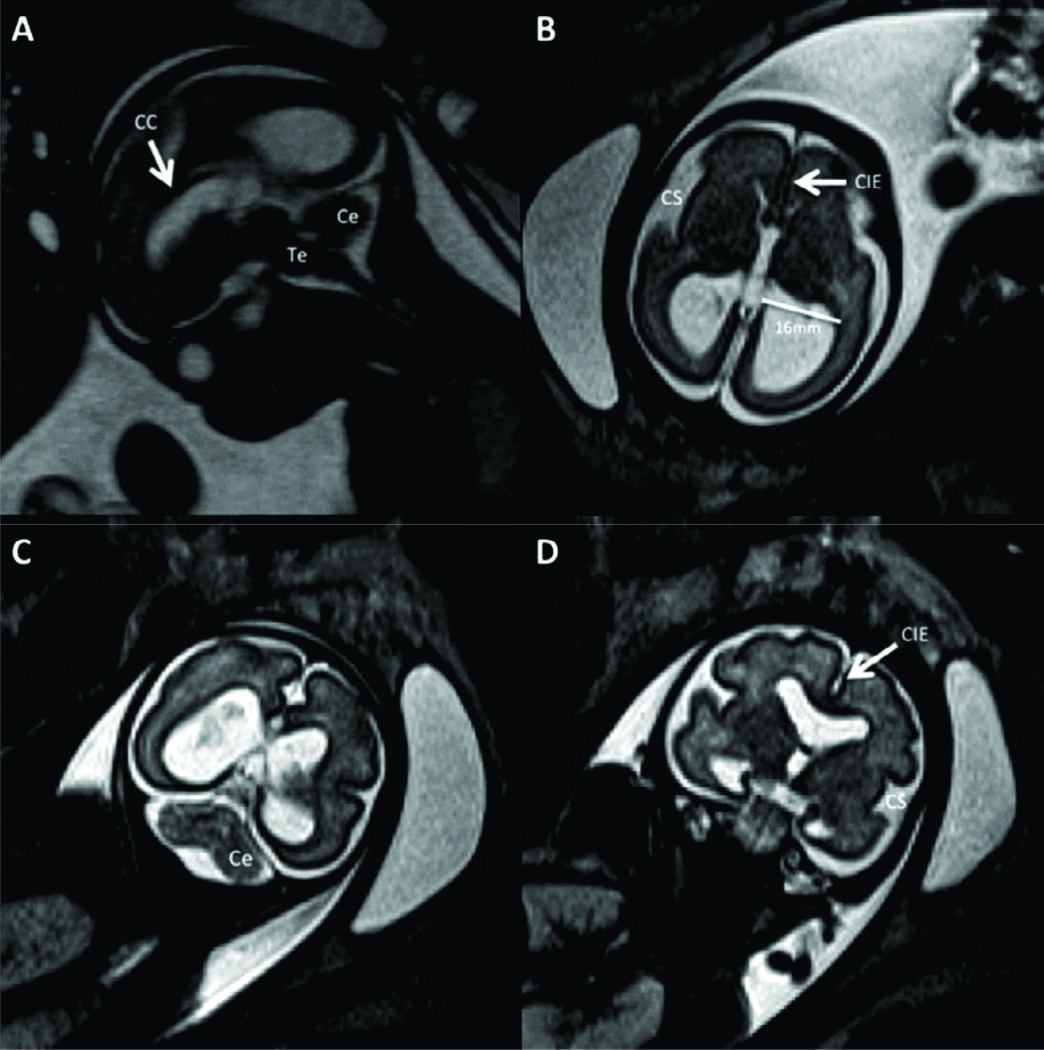

Figura 3

RM Fetal con Ventriculomegalia (Edad Gestacional: 28 semanas).

Imágenes seleccionadas de RMf en paciente referido por estudio ecográfico que muestra aumento del tamaño del sistema ventricular.

En A imagen en línea media donde se reconocen las estructuras normales: cuerpo calloso (CC), tronco encefálico (Te) y cerebelo (Ce) con su aspecto habitual.

En B el corte axial a nivel de los atrios ventriculares donde se evalúa el tamaño ventricular (16mm del lado izquierdo) y se reconocen la cisura inter-hemisférica completamente formada (CIE) y la cisura de Sylvio en la convexidad (CS).

En C y D cortes coronales que complementan la valoración anatómica. Luego del análisis preciso de todo el estudio no se encontraron otras anomalías asociadas.

;

Figura 4

RM Fetal Hidrocefalia por Estenosis del acueducto.

Se presentan 2 casos de fetos con hidrocefalia (HCF) por estenosis del acueducto. El primer caso se presenta con HCF leve/moderada (A sagital y B axial) donde puede observarse la dilatación ventricular supra-tentorial con IV ventrículo normal lo que orienta al diagnóstico de estenosis del acueducto.

En C se muestra imagen sagital del 2º caso con HCF severa y ausencia de señal en el acueducto de Sylvio lo que orienta al diagnóstico (è). AV: Atrio ventricular

CC: cuerpo calloso

Te: Tronco encefálico

Ce: Cerebelo